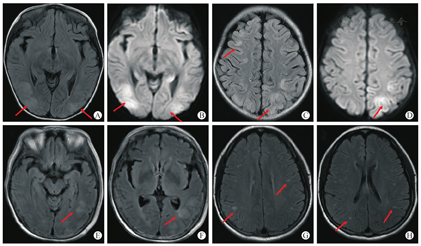

受者,女,6岁,2021年3月因"先天性胆道闭锁,胆汁性肝硬化失代偿期"于华中科技大学同济医学院附属同济医院行肝移植术。术后第2天给予他克莫司+吗替麦考酚酯(MMF)+泼尼松三联免疫抑制治疗,移植肝功能恢复顺利。术后第4天早晨该儿童出现神志淡漠、视物不清、听力下降,并间断抽搐,神经系统检查无定位体征。当晚症状加重,表现为间断癫痫发作、呼之不应,呈浅昏迷,血压152/102 mmHg,心率149次/分,体温38.4℃。予以镇静(咪达唑仑)、降颅压(甘露醇)、降血压及降温等对症处理后癫痫症状消失,各项生命体征恢复平稳。该儿童受者发作前血压正常,他克莫司血药浓度11.0 μg/L。急诊头颅CT平扫提示双侧顶叶低密度影,进一步MRI检查提示双侧额颞顶枕叶、丘脑、部分海马T2液体衰减反转恢复序列(FLAIR)多发异常高信号灶,皮层受累为主,扩散加权成像(DWI)呈高信号(图1A-D),结合临床考虑为PRES,遂停服他克莫司改服环孢素A并继续对症处理。治疗5d后上述症状完全消失。目前术后随访14个月,肝功能稳定,无神经系统后遗症。

受者,女,62岁,2021年8月因"慢性肾脏病5期"于华中科技大学同济医学院附属同济医院行肾移植术。术后第2天给予他克莫司+MMF+泼尼松三联免疫抑制治疗,移植肾功能恢复顺利。术后第8天受者陆续出现头痛、睡眠障碍和间断性神志淡漠等症状,予以对症处理未见明显好转。术后第13天该受者突发癫痫,伴有右下肢肌力下降,血压113/78 mmHg。受者发作前血压控制稳定,他克莫司血药浓度16.8 μg/L。头颅MRI检查显示左侧颞枕叶皮层下多发不规则点状及条索状长T1长T2 FLAIR信号(图1E-F),结合临床考虑为PRES。予以镇静(地西泮)、降颅压(甘露醇)和他克莫司减量,癫痫症状缓解,治疗6 d后受者神志恢复正常。经过2周康复治疗后,受者下肢肌力恢复。目前术后随访9个月,移植肾功能稳定,无神经系统后遗症。

受者,女29岁,2022年3月因"慢性肾脏病5期"于华中科技大学同济医学院附属同济医院行肾移植术。术后第2天给予他克莫司+MMF+泼尼松三联免疫抑制治疗,移植肾功能恢复顺利。术后第15天该受者出现左侧枕叶搏动性头痛,数小时后突发癫痫,意识丧失,血压124/83 mmHg。受者发作前血压控制稳定,他克莫司血药浓度11.6 μg/L。急诊头颅CT平扫未提示异常,予以镇静(地西泮)、降颅压(甘露醇)和他克莫司减量,癫痫症状缓解,但受者仍感头痛伴耳鸣,头颅MRI显示双侧额顶叶多发斑点状等及稍长T1、T2 FLAIR信号(图1G-H),结合临床考虑为PRES,继续上述治疗,11 d后头痛消失。目前术后随访3个月,复查MRI显示头颅异常病灶消失,移植肾功能稳定,无神经系统后遗症。